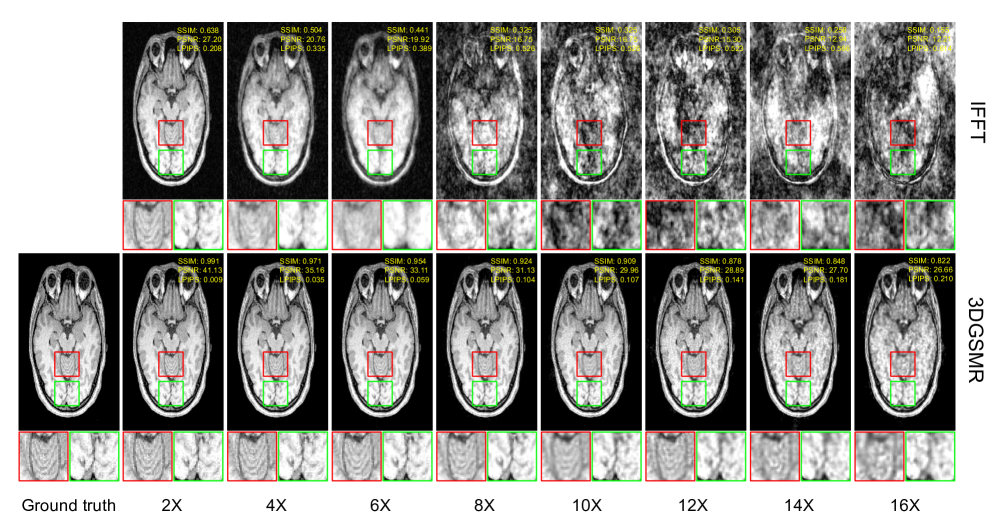

Refer to caption

Figure 6: Showcase of the reconstruction results for acceleration factors 2, 3, 4, 6, 8, 10, 12, 14, and 16 from one dataset. The proposed framework demonstrates robust performance across different acceleration factors. As the acceleration factor continues to increase, the reconstructed images become more blurred, hindering the details in the images. Two regions in the selected coronal slice are zoomed in for better visual comparison.

IV-D Effectiveness of the proposed framework

This section presents the reconstruction results across different acceleration factors. Figure 6 shows the reconstructions for different acceleration factors using the proposed framework as well as direct iFFT on one dataset. Two regions in the selected coronal slice containing gray matters and white matters are magnified for further visual comparison. As the acceleration factor increases, the white matter and gray matter regions from the iFFT reconstruction become increasingly blurred and noisy, making it difficult to distinguish the details. While the proposed 3DGSMR framework is able to resolve these artifacts and reconstruct the details in the images.

In Figure 6, quantitative results using SSIM, PSNR, and LPIPS are also present on each image. The iFFT results are used as the baseline to highlight the improvement of the proposed framework. The improvements from the quantitative perspective provided by the proposed 3DGSMR scheme demonstrate its effectiveness for isotropic resolution 3D MRI reconstruction.